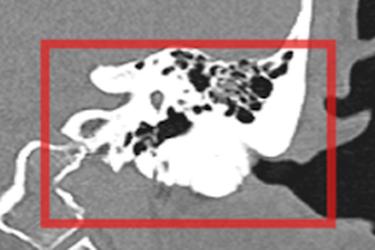

Giảm thính lực do lồi xương ống tai ngoài hiếm gặp

Một người phụ nữ bị giảm thính lực do lồi xương ống tai ngoài hiếm gặp.